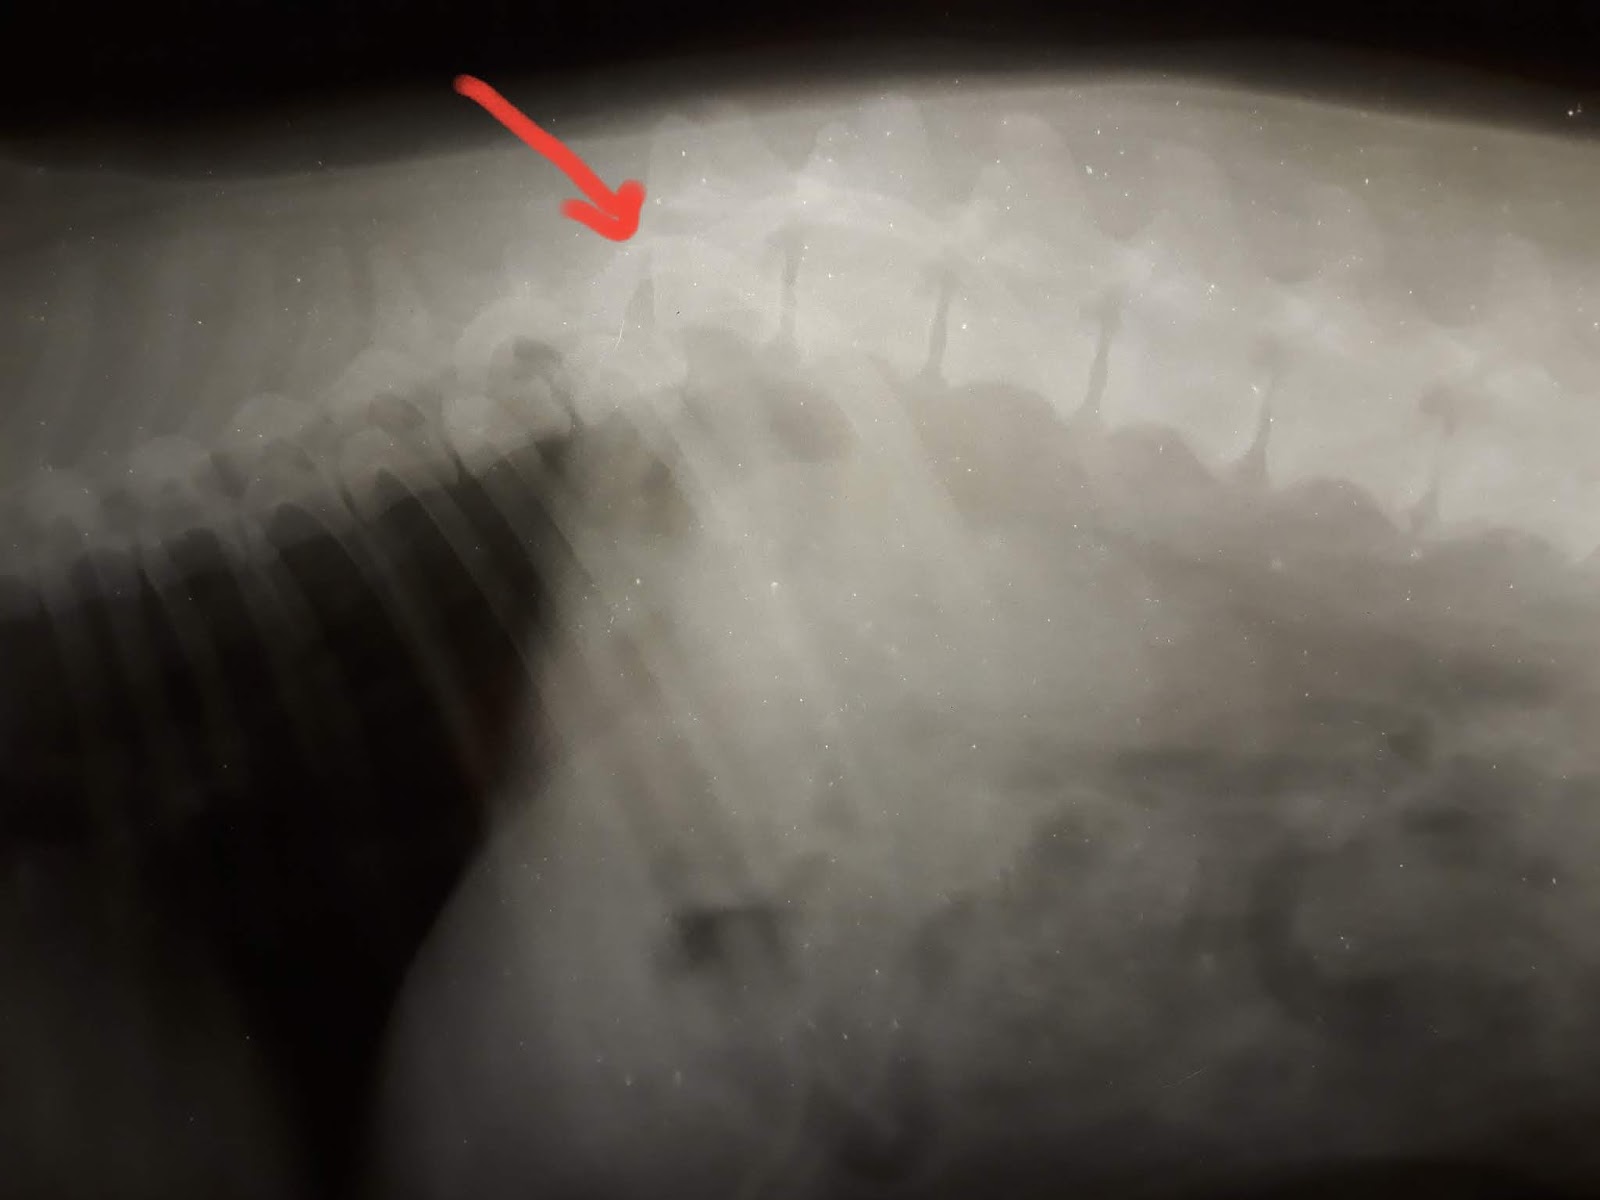

Заболевания позвоночника у домашних животных: диагностика и лечение

Раздел: Визуальные истории